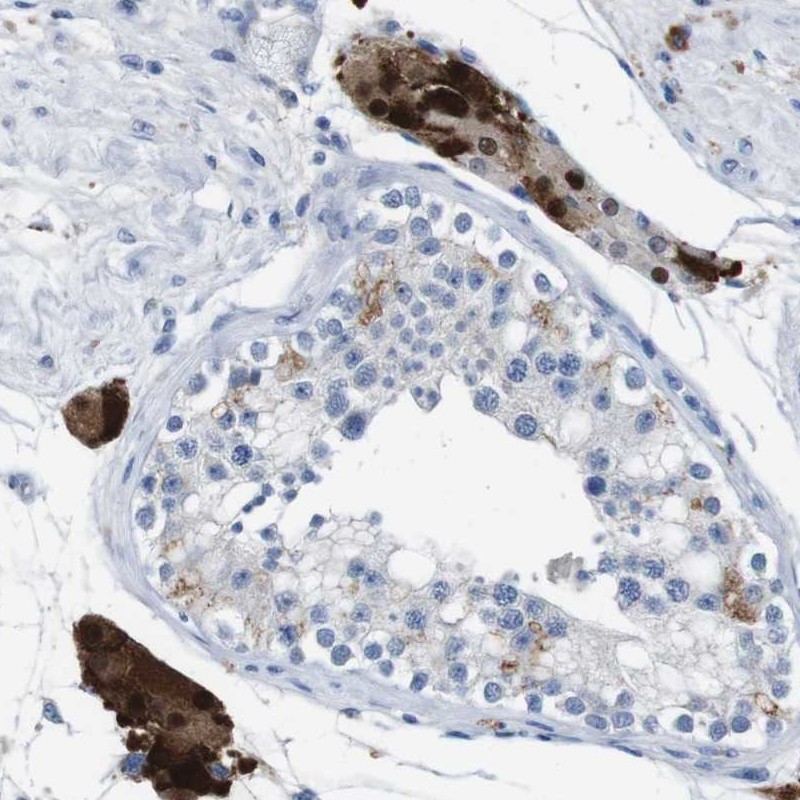

Immunohistochemical staining of human testis shows strong nuclear and cytoplasmic positivity in cells of seminiferus ducts.